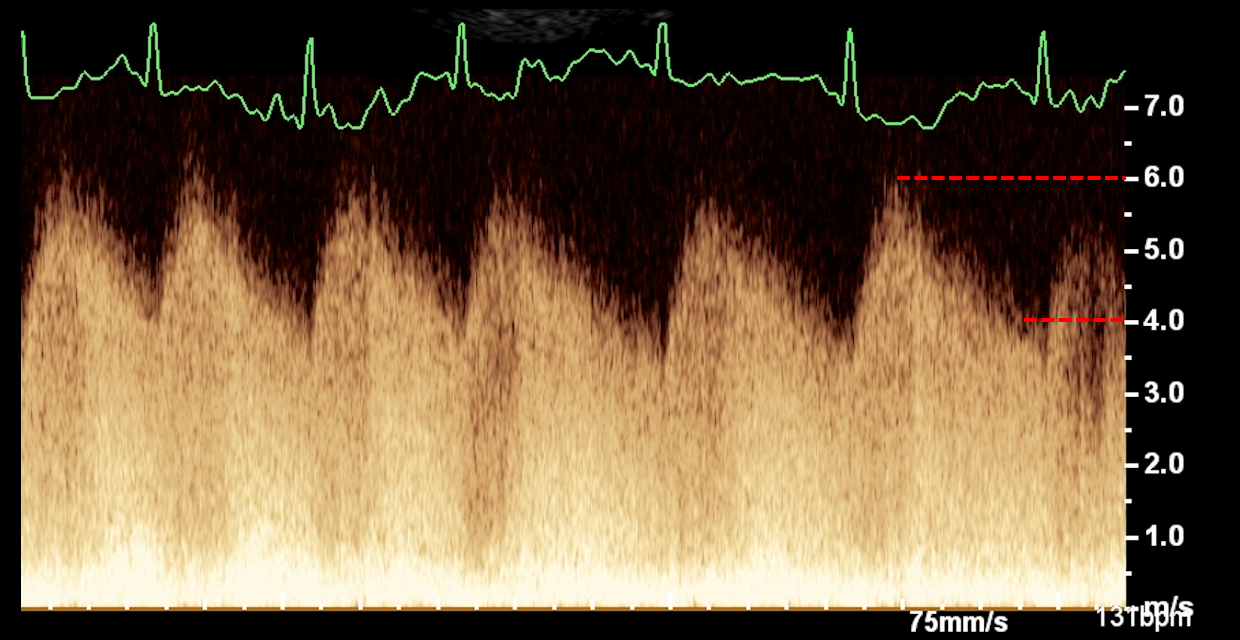

• Utiliser les anomalies observées en modes 2D, TM et Doppler pour classifier et graduer les cardiopathies acquises.

• Savoir interpréter de manière croisée les données issues du Doppler et celles issues des modes 2D et TM.

• Étude de cas interactifs à partir d’images fixes et de vidéos en échographie cardiaque (modes 2D, TM, Doppler).

• Principes de l’échocardiographie 2D, TM et Doppler appliqués aux cardiopathies acquises.